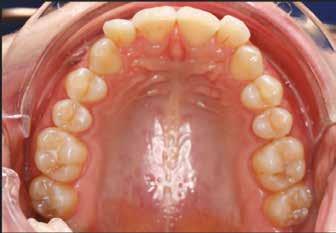

A páciens fogazata esztétikai megjelenésének és funkcionális működésének a lehető legtöbb, saját foganyag megtartása mellett történő helyreállítása (1. és 3. ábra).

A kezelés megtervezése során kifejezett jelentősége van annak, hogy jó kommunikáció legyen a páciens, a fogorvos és a fogtechnikus között. A páciens leendő fogazatának természetes megjelenését a kezelésben részt vevő team szakmai felkészültsége, gyakorlati tapasztalata és a kezelés sikerességének irányába történő elkötelezettsége biztosítja. A beavatkozások megkezdése előtt megtörtént a páciens anamnézisének a felvétele, valamint a klinikai kivizsgálását is elvégeztük. Ezt követően lenyomatokat készítettünk a kiindulási állapotról, majd a kiindulási helyzetet extra- és intraorális fotók segítségével is rögzítettük (13. a-c. ábra).